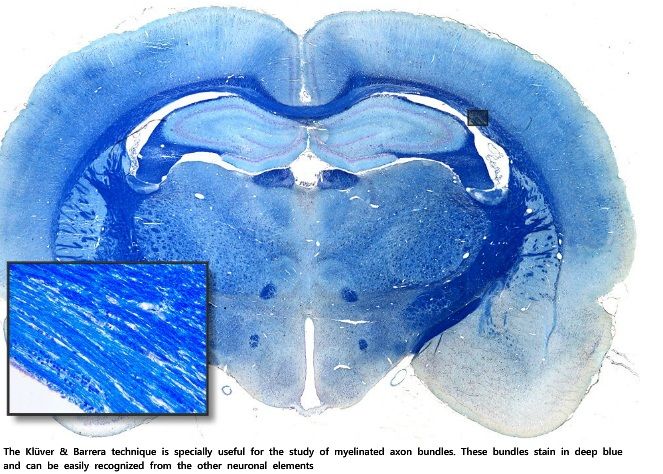

2. Klüver y Barrera

1. Esta técnica es específica del estudio del cerebro. Muestra somas neuronales teñidos de un color azul-violeta, el parénquima nervioso de color azul pálido y, lo más significativo, los axones mielínicos se tiñen de color azul intenso. Evidentemente esta técnica se usa para el estudio de los diferentes haces de fibras mielínicas del cerebro y ha permitido establecer las grandes rutas de comunicación entre las diferentes zonas del cerebro.

1. Corte: de 8 um de grosor